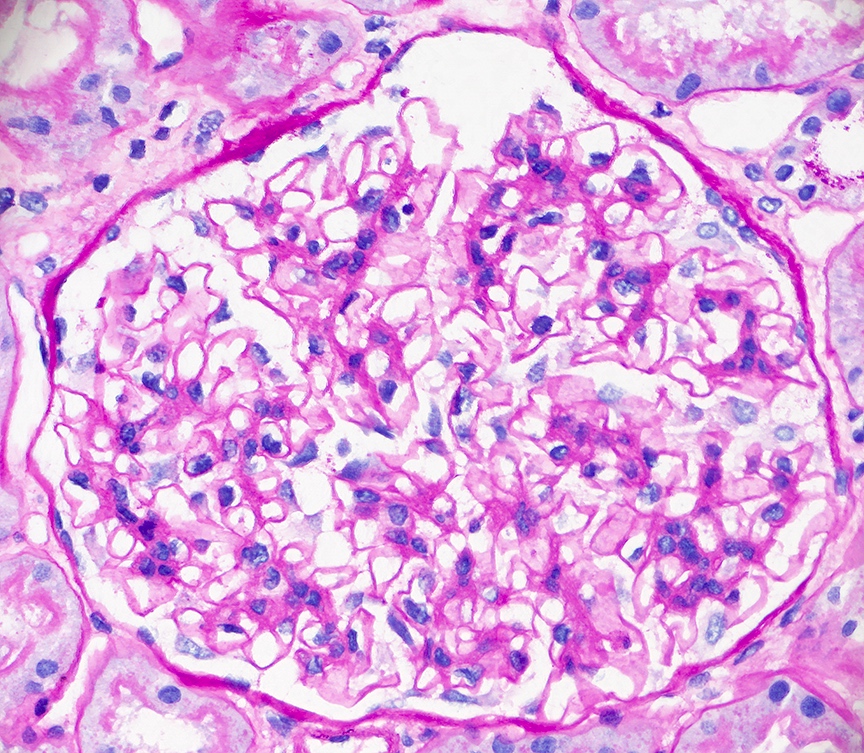

Microscopic (histologic) images

Contributed by Alexei Mikhailov, M.D., Ph.D.

Microscopic (histologic) description

- LN class I: normal glomeruli by light microscopy

- LN class II: mesangial hypercellularity or mesangial matrix expansion

- LN classes III - IV: lesions may be active (endocapillary or extracapillary proliferation) or chronic (sclerosing)

- Wire loop deposits, hyaline microthrombi, membranoproliferative lesions

- Fibrinoid necrosis and karyorrhexis may be present

- LN class V: thickening of the glomerular capillary walls, microspikes and domes may be associated with any mesangial alterations

- LN class VI: extensive glomerular sclerosis